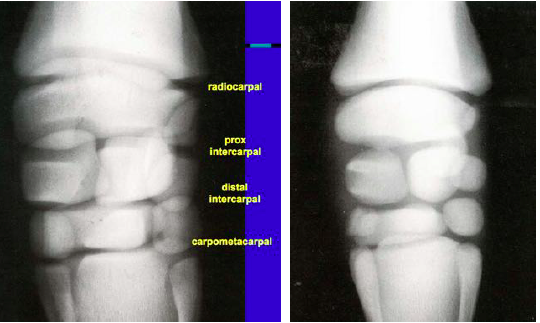

You take a radiograph of a foal and see this. What is happening in this carpus?

Incomplete ossification leading to rounded carpal bones. This contributes to instability of the joint space, resulting in either varus or vaglus deformities.

See normal radiograph on left. There should be some degree of increased joint space in young animals d/t the presence of more cartilage.